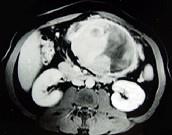

问题 男,36岁,腹胀、消化不良、消瘦、中上腹痛,影像检查如下图,最可能的诊断是 ( )

选项 A.胃间质肉瘤并肝转移 B.胃间质瘤并原发性肝癌 C.内胚窦瘤肝转移 D.胃淋巴瘤伴原发性肝癌 E.胃间质瘤并肝血管瘤

答案 A